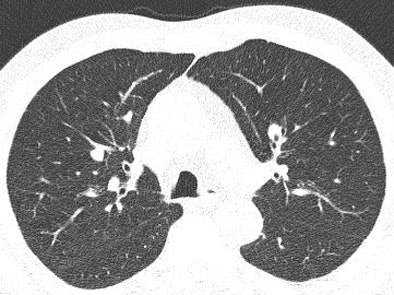

The study looked at 20 datasets selected from patients with known intrapulmonary nodules. Images were acquired on a Siemens Somatom 16 scanner at 120 kVp, effective 100 mAs, 16 x 1.5-mm collimation, 2-mm-thick sections with 1.5-mm reconstruction intervals, and with a standard lung reconstruction kernel.

The raw data were processed by artificial noise software to simulate exposure using 10 effective mAs before being run through the CAD, and the results compared. Image noise was quantified by measuring the standard deviation in Hounsfield units of a syringe placed on the patient's sternum during imaging.

In all, 113 nodules (one to 13 nodules per case, average six; average size 78 mm3) were found by a consensus panel of two experienced radiologists with access to all imaging and CAD data.

![]() |

| Low-dose image (above) shows greater image noise than full-dose image below, which can affect the nodule detection algorithm. Images courtesy of Dr. Marco Das. |

Compared with the expert readers, standard-dose CAD had an overall sensitivity of 77.6%, with a per-patient sensitivity of 84% and 1.8 average false positives per case. At the low-dose settings, CAD found 64 nodules for an overall sensitivity of 55% with a per-patient sensitivity of 67% and 1.5 false-positives per case. Interestingly, Das said, there was no statistically significant difference in false positives between the two settings.

Most nodules missed on CAD at the low-dose settings were smaller than 6 mm, he said.